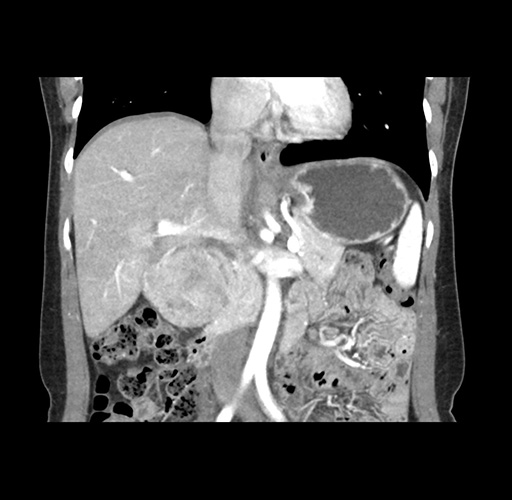

Imaging Analysis

Look through the patient's CT scan to identify any areas of concern for the necessary procedure.

Based on your CT findings, which issue(s) would give reason for "planned slowing down moment(s)" in this case?